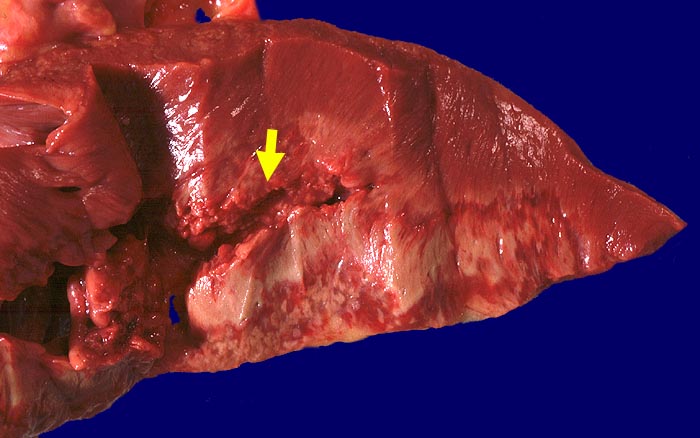

PathoPic – image database / PathoPic ID 761 - Subakuter Myokardinfarkt der Vorderwand mit Ruptur

Subakuter Myokardinfarkt der Vorderwand mit Ruptur

Scharf begrenztes lehmfarbenes infarziertes Areal umgeben von einem breiten roten Randsaum Granulationsgewebe. Rupturstelle im Bereich des Granulationsgewebssaums.

Subakuter Myokardinfarkt von Vorder- und Hinterwand. Myokardruptur mit Hämatoperikard. Schwer stenosierende Sklerose von Ramus circumflexus der linken Koronararterie und der Arteria coronaria dextra.